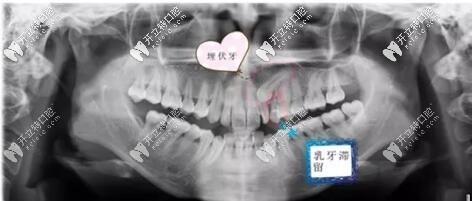

桂林七星區(qū)兒童牙科曝光:7歲埋伏牙正畸牽引成功病例

桂林七星區(qū)的周瑾帆口腔是一家專門治療兒牙的醫(yī)院,不少人問瑾帆口腔治療效果怎么樣?今天拿埋伏牙矯正牽引成功效果來給大家亮個相。